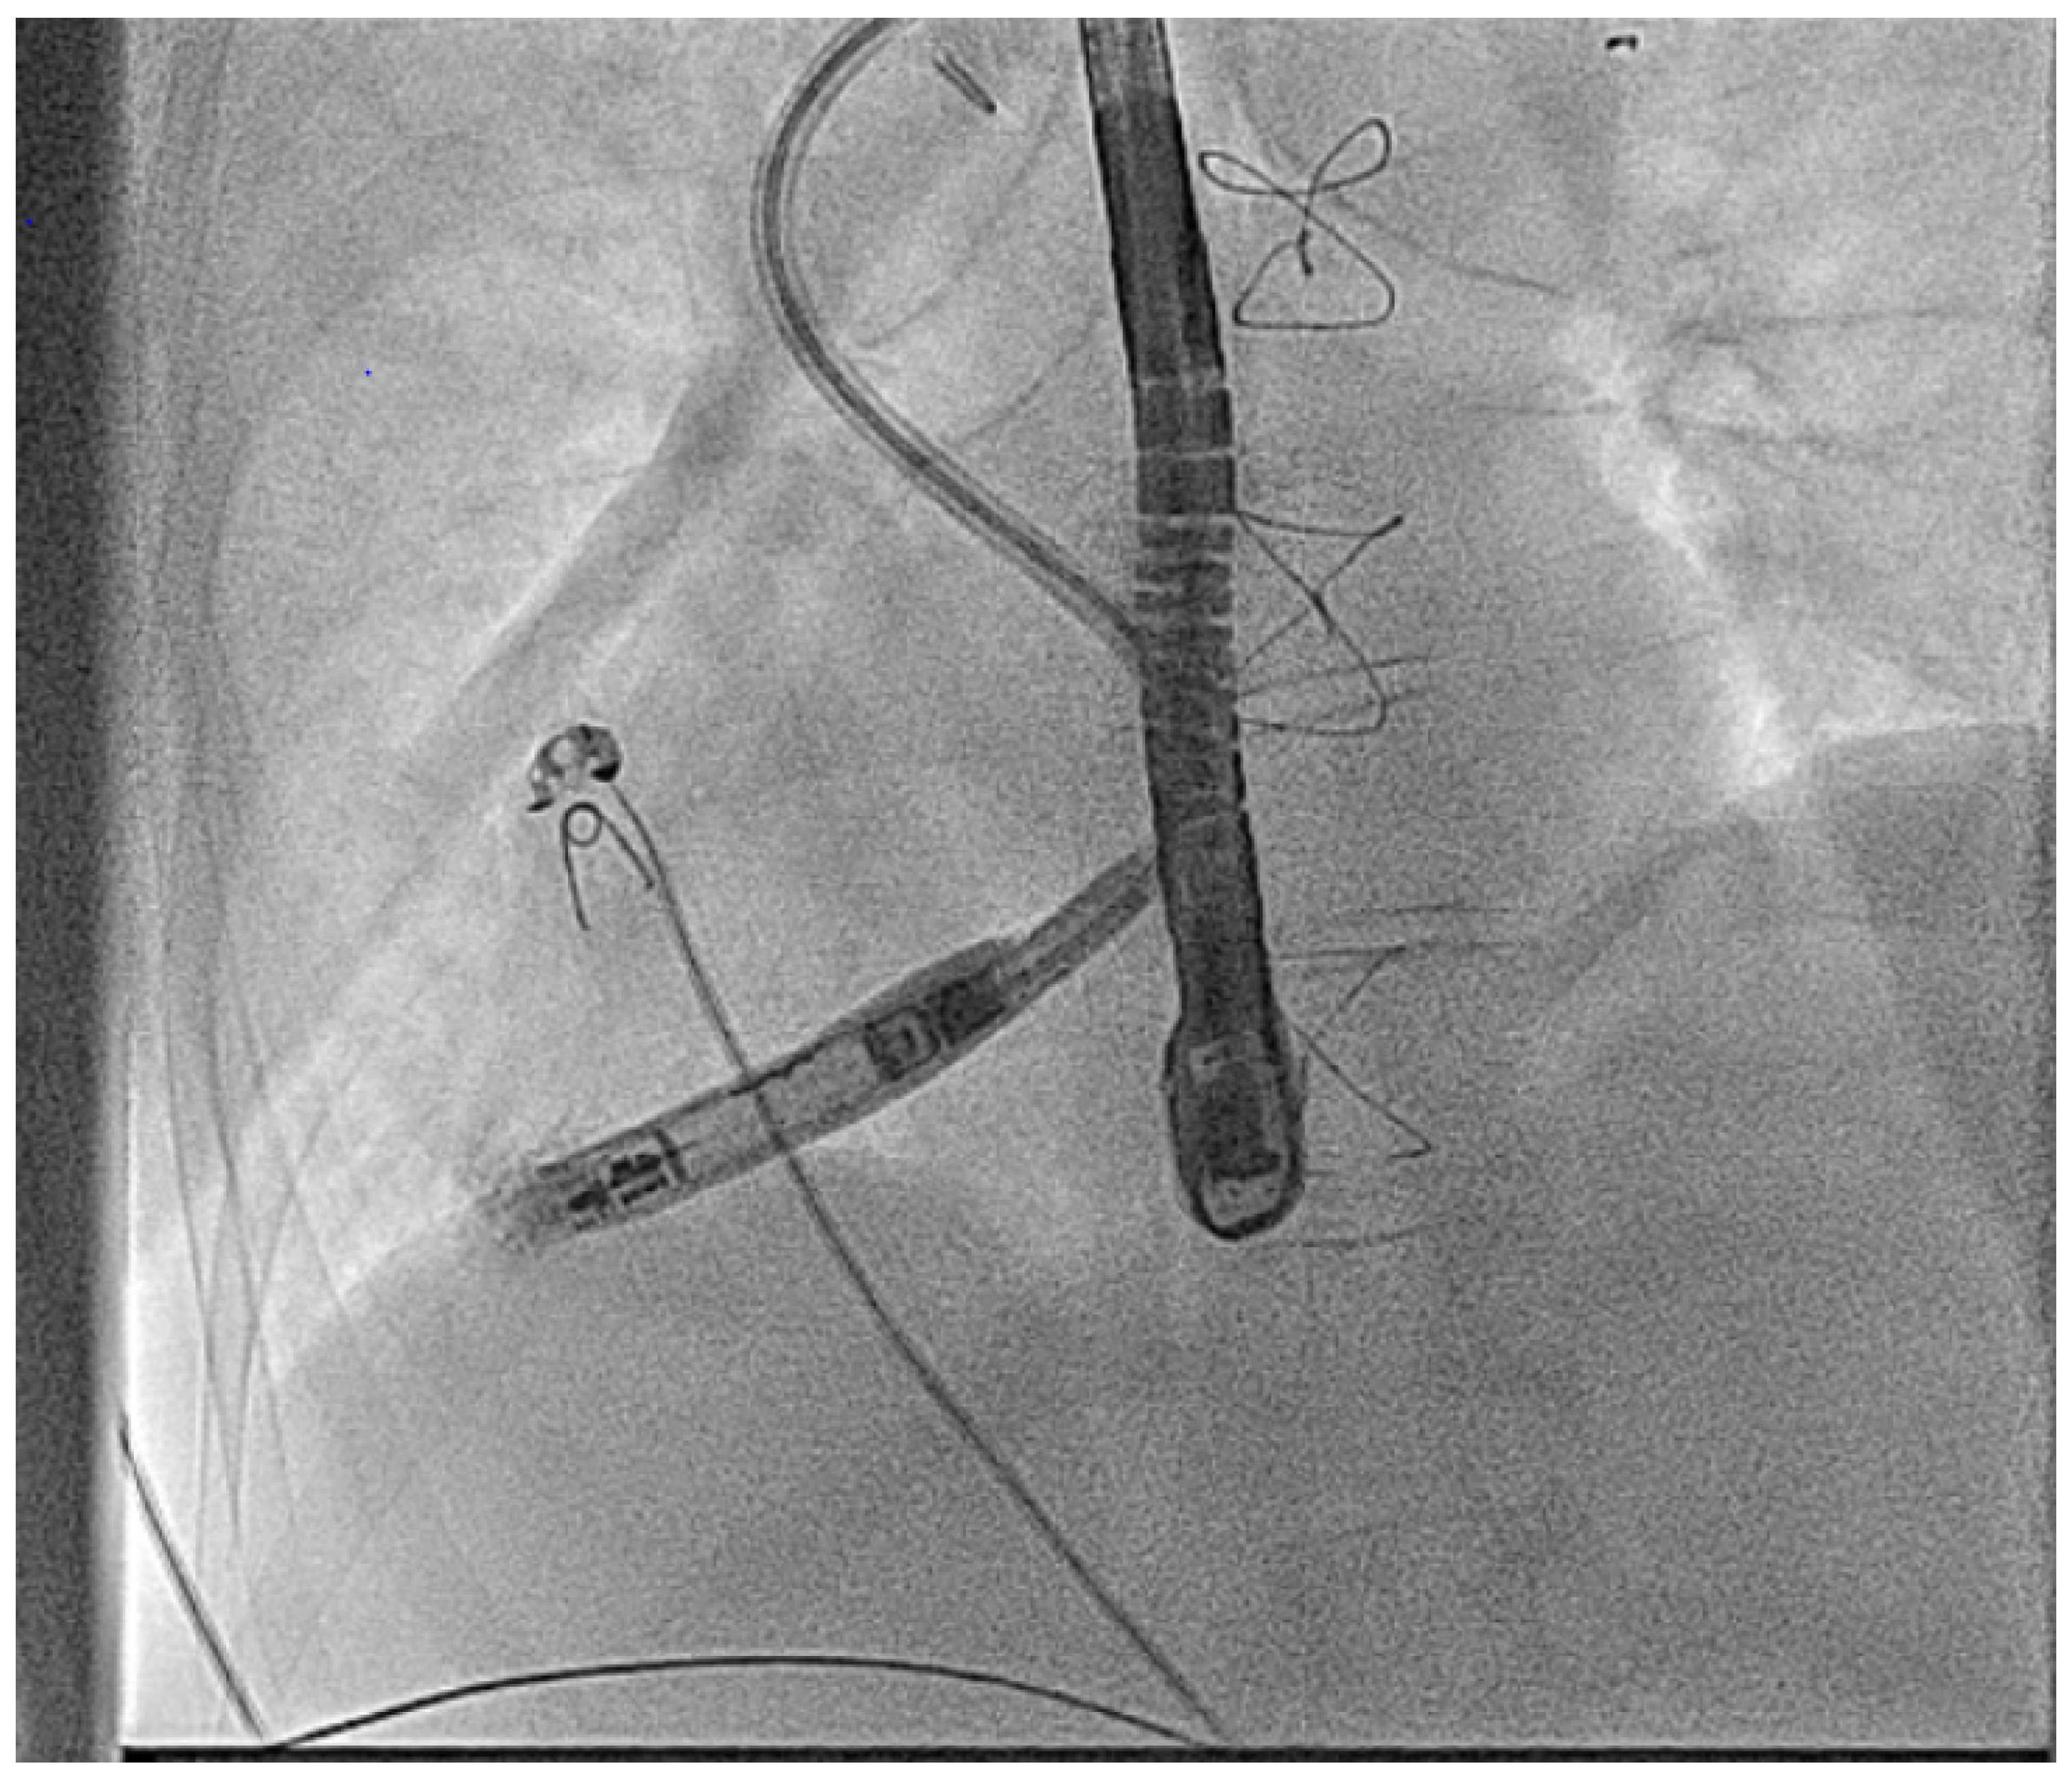

- Hayle, P.; Altayeb, F.; Hale, A.; Rao, A.; Ashrafi, R. Case report demonstrating novel approaches for leadless pacemaker implantation in the single ventricle heart. Eur. Heart J. Case Rep. 2025, 9, ytaf146. [Google Scholar] [CrossRef]

- Goulden, C.J.; Khanra, D.; Llewellyn, J.; Rao, A.; Evans, A.; Ashrafi, R. Novel approaches for leadless pacemaker implantation in the extra-cardiac Fontan cohort: Options to avoid leaded systems or epicardial pacing. J. Cardiovasc. Electrophysiol. 2023, 34, 2386–2392. [Google Scholar] [CrossRef]